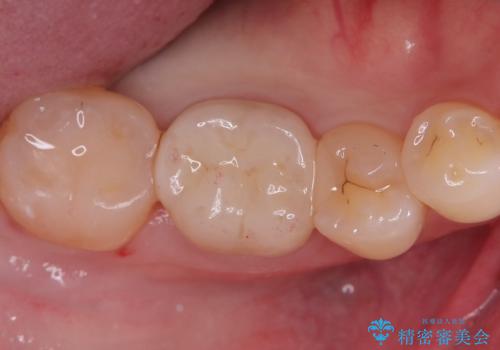

- 主訴:銀色の詰め物が取れてしまった。下の歯は笑うと見えるので、これを機に白くしたい。

保険適用のメタルインレーが脱離しており、歯冠色で審美性、適合性の良いセラミックインレーでのやり替えを提案しました。

メタルインレーが脱離した咬合面の窩洞内は、う蝕を除去し、セラミックインレーの厚みの担保とメタルタトゥー部分の除去を目的に形成を行いました。

インレーセット時はラバーダム防湿を行っています。